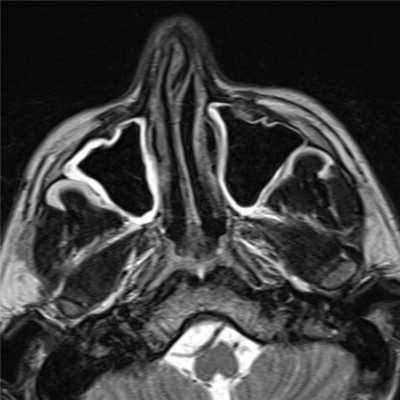

(Слева) При аксиальной КТ без КУ визуализируется большой полип, заполняющий полость носа справа, и выбухающий из правой ноздри. Обратите внимание на доброкачественное ремоделирование костей и смещение влево костной носовой перегородки. Уровни «жидкость-газ» с пузырьками газа в верхнечелюстных пазухах неспецифичны и могут быть обусловлены воспалительным компонентом при остром синусите.

(Справа) При аксиальной MPT Т2ВИ у пациента с тяжелым полипозом визуализируются множественные гиперинтенсивные полипы, заполняющие полость носа и внутренние отделы верхнечелюстных пазух.